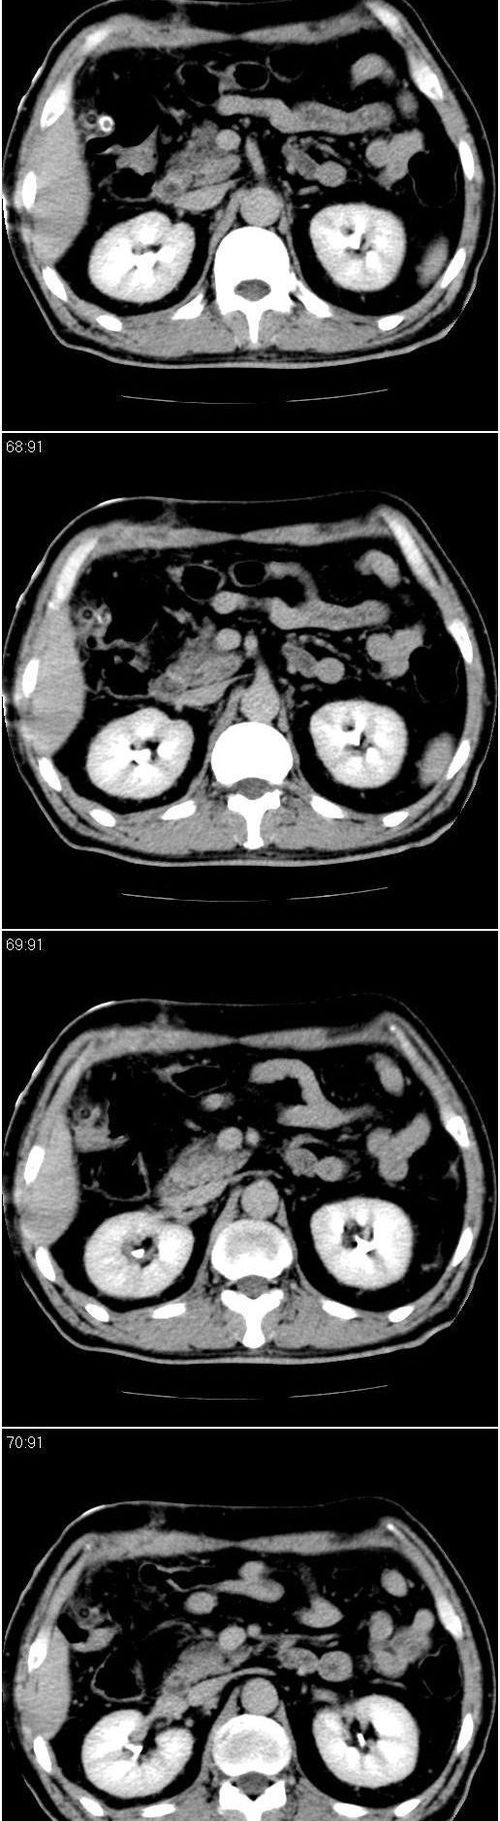

标题: CT13147:男,57岁。因胆结石阻塞性黄疸入院。 [打印本页]

标题: CT13147:男,57岁。因胆结石阻塞性黄疸入院。

男,57岁。因胆结石阻塞性黄疸入院。这是胆囊切除术后的照片,看看此片到底有什么问题。

在手术切除胆囊的过程中,发现肝门部胆总管恶性占位,因为家属不同意手术,没有切除,能看出来么?

现有资料很难说,薄层可能清楚些,如临床不提供,易诊断为术后改变。

此片看不出,难道术前没查ct?

肝内外胆管轻度扩张。楼主提示左右肝管合汇区域壁稍厚。胆总管末段壁似也稍厚有轻度强化。就现有资料诊断难。